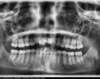

Canine incluse traitée avec des gouttières

Début de traitement